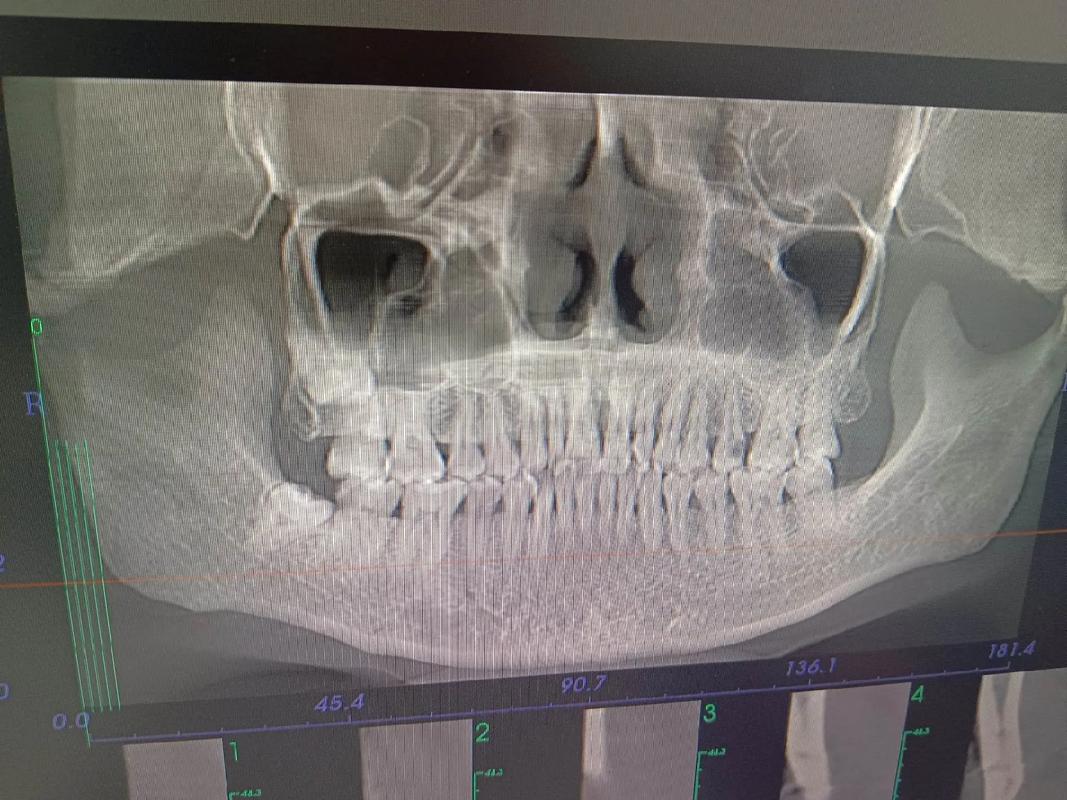

- 对于一些复杂的、涉及骨骼、埋伏牙、种植支抗或需要精确评估骨量的情况,口腔CT(CBCT)是极其重要甚至不可或缺的诊断工具。

- 埋伏牙定位: 对于未萌出的牙齿(如埋伏阻生智齿、尖牙、多生牙),CBCT能清晰显示牙齿在颌骨内的精确位置、萌出方向、牙根形态以及与邻牙、重要解剖结构(如下颌神经管)的关系,这是二维片无法比拟的,对制定手术导萌或正畸牵引方案至关重要。

- 牙根位置与吸收: 可以清晰观察牙根在牙槽骨内的位置、有无弯曲、以及是否有牙根吸收(尤其是正畸治疗过程中或治疗后需要评估时)。

- 牙槽骨量评估: 在需要植入种植体作为支抗(如种植支抗钉)或评估拔牙后牙槽骨情况时,CBCT能精确测量牙槽骨的厚度、高度、密度,判断是否足够容纳种植体或支持牙齿移动。

- 颌骨形态与不对称: 对于严重的颌骨发育问题(如下颌偏斜、面部不对称),CBCT能提供颌骨三维形态的详细信息,帮助制定复杂的正畸正颌联合治疗方案。

- 颞下颌关节(TMJ)评估: 当怀疑有关节盘移位、骨关节病等问题时,CBCT能清晰显示关节骨性结构的变化。

- 牙根移动模拟: 在数字化正畸中,CBCT数据可以与口内扫描数据结合,建立精确的三维牙颌模型,进行虚拟牙齿移动模拟,预测治疗结果,制定更精准的方案。

- 气道评估: 对于有睡眠呼吸暂停倾向或需要评估气道空间的患者(尤其涉及下颌后缩或上颌垂直向发育问题),CBCT可以测量咽腔容积和横截面积,辅助诊断和治疗决策。

- 正畸手术规划: 对于需要正颌手术的患者,CBCT是手术模拟和制定手术方案的基础。

- 复杂正畸: 当涉及埋伏牙、种植支抗、骨骼问题、精确骨量评估、疑难杂症等情况时,口腔CT(CBCT)是非常必要的诊断工具,能提供二维影像无法企及的关键信息,有助于制定更精准、更安全、更可预测的治疗方案,并降低治疗风险。